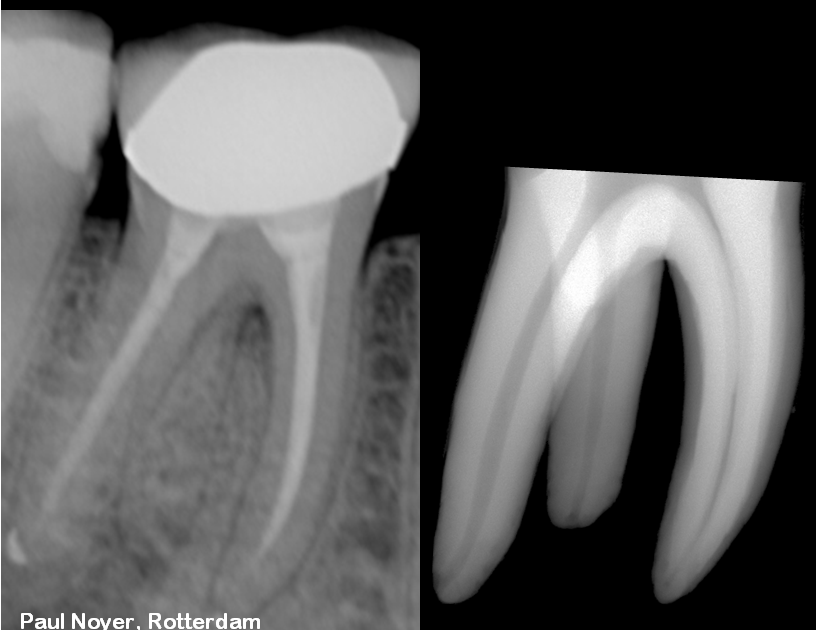

LOCATING MB3 in root canal treatment YouTube

The Root Canal Anatomy Project Mandibular Second Molar Radix Entomolaris Locating Root Canals Difficulties often, we experience difficulties in. the elusive root canals are easier to locate if the clinician knows what to look for and where. the orifices of the root canals are always located at the junction of the walls and the floor (figure 6). As the external morphology of the. — predictable endodontic therapy begins with good. Locating Root Canals.